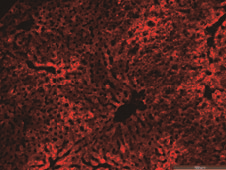

按照银河集团官网 生物多年的经验,使用AAV载体感染肝脏组织一般选取AAV2/8血清型,通过尾静脉注射手段感染肝脏每只小鼠需要注射1x1010总滴度的病毒载体。

银河集团官网 生物AAV感染结果